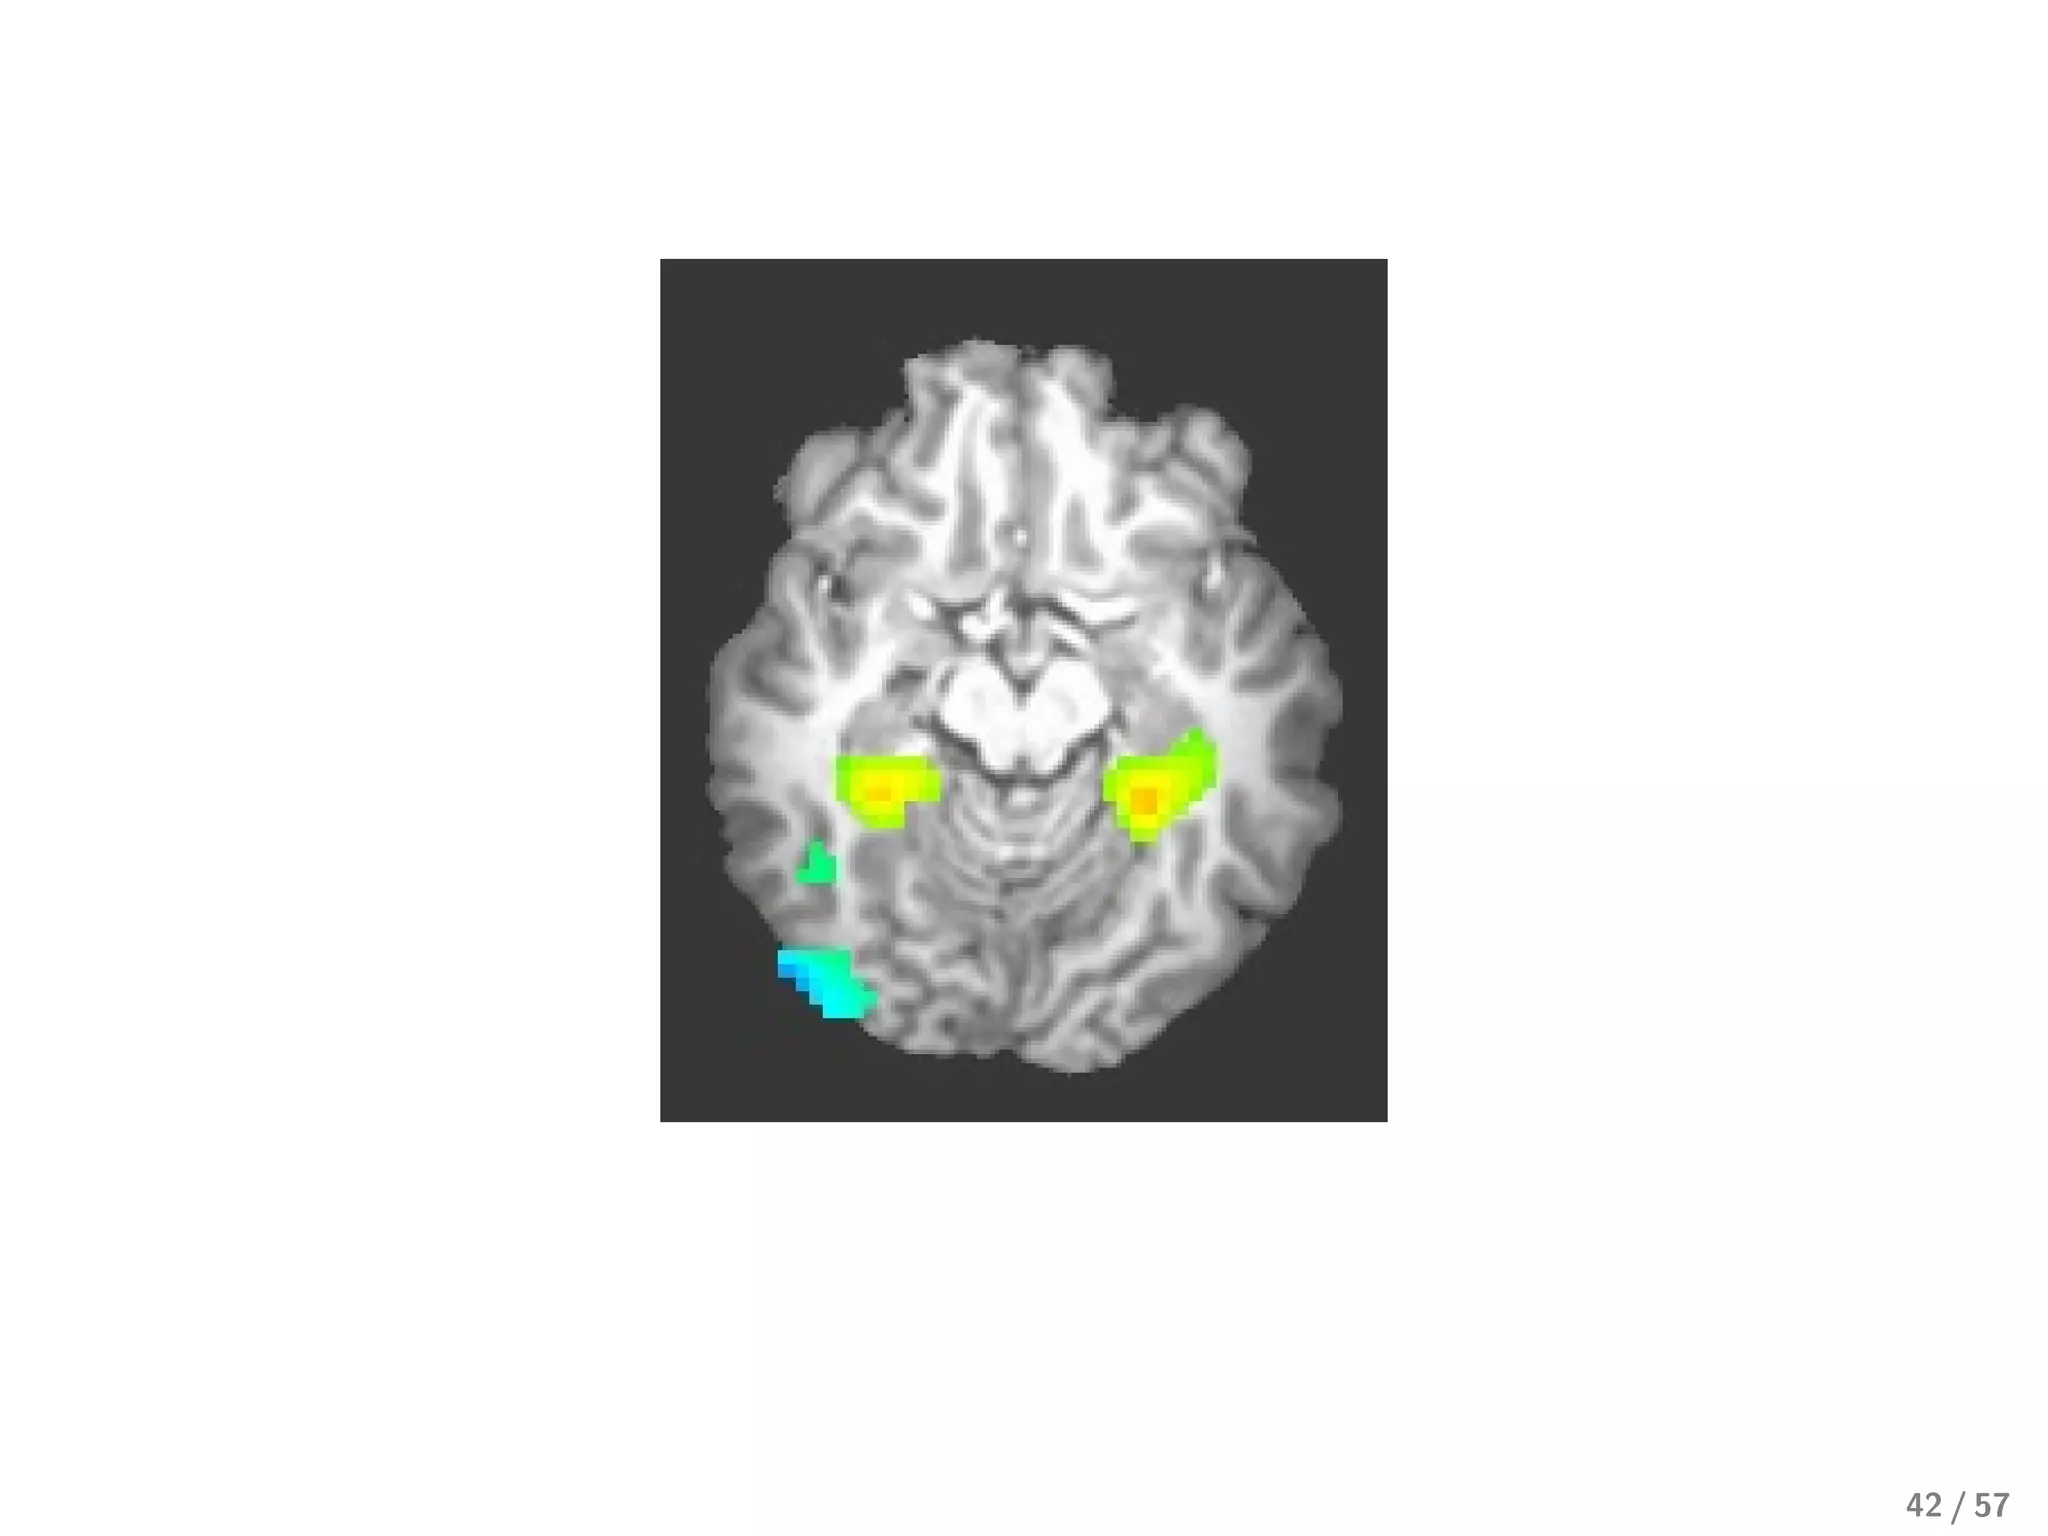

From neurology, we know we should expect large clusters of voxels

41 / 57

Best current approach: mix L1 and L2

From neurology, weknow we should expect large clusters of voxels 41 / 57

• 42.

Best current approach:mix L1 and L2 43 / 57